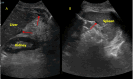

Clostridium difficile (CD) is a spore-forming, Gram-positive anaerobic bacillus that causes toxin-mediated mucosal injury leading to pseudomembranous colitis, clinically characterized by diarrheal disease. Ascites is an infrequent manifestation in severe or fulminant CD colitis. The pathogenesis of ascites in CD colitis is poorly understood but includes hypoalbuminemia due to protein-losing enteropathy, transmural inflammation, toxin-mediated capillary leak, colonic perforation, and concomitant diseases. We report the case of a middle-aged woman who presented with an opioid overdose and subsequently developed severe CD colitis. The infection was complicated with low serum-ascites albumin gradient (SAAG), high protein, culture-negative, neutrophil-predominant ascites, devoid of visceral perforation, or an alternative etiology for ascites. Treatment with oral vancomycin and intravenous metronidazole led to the complete resolution of symptoms and ascites. This case highlights an uncommon presentation of a common healthcare-associated infection and reinforces the importance of recognizing atypical manifestations of CD. While there are no specific management guidelines for this subset, treating the underlying colitis appears sufficient to resolve the ascites in most cases.